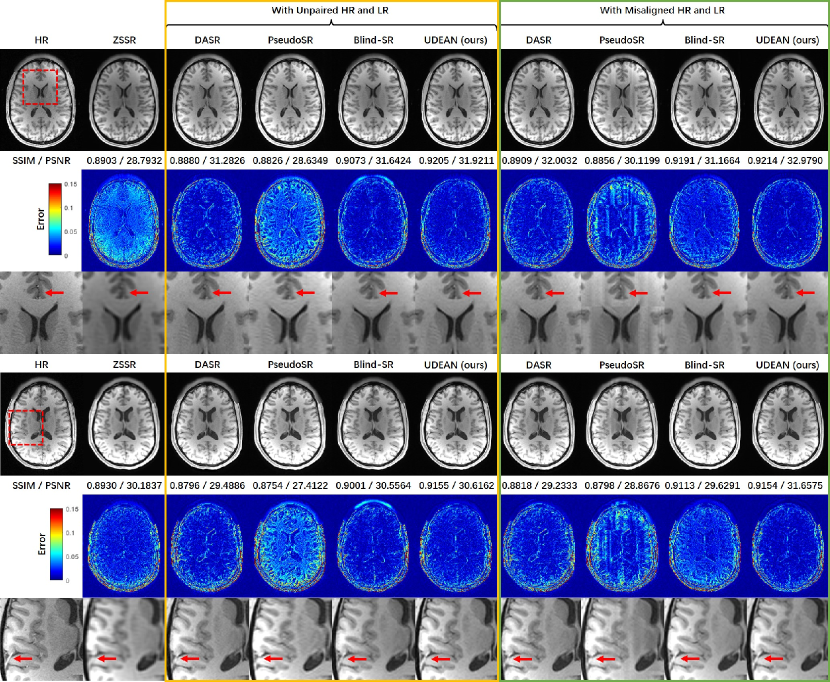

Refer to caption

Figure 5: Comparison of reconstructed SR images and error maps of supervised learning and different configurations of the UDEAN with misaligned LR and HR image pairs of the HCP dataset and the scale factor of 2×2×22222\times 2\times 2 in the axial plane. The SR images reconstructed using supervised learning are highly blurry. The

We evaluated our network in various configurations on the same task of SRR for misaligned LR and HR datasets to find the best performance. The effect of DA in the image space and latent feature space was evaluated. Besides, we compared our network to the same backbone network trained in the supervised strategy with the misaligned training data to reveal the effect of the degradation-learning modules. As shown in Table 1, all the configurations of the UDEAN outperformed the supervised learning using the same generator by over 0.014/0.74 dB in SSIM/PSNR using misaligned LR and HR image from the HCP dataset with the scale factor of 2×2×22222\times 2\times 2. Among the configurations of the UDEAN, the performance was downgraded by 0.009/0.75 dB or 0.002/0.71 dB in SSIM/PSNR when DA in only latent feature space or image space was applied, respectively.

Furthermore, Fig. 5 shows the visual effect of the reconstructed SR images and the error maps to the HR images. The SR image reconstructed by the supervised methods were highly blurry either with or without rigid image registration. On the contrary, the quality of SR images reconstructed by the UDEAN was significantly improved even with DA only in latent feature space or image space. The errors of the reconstructed anatomical structures were further reduced when DA in both domains was applied in the training process.